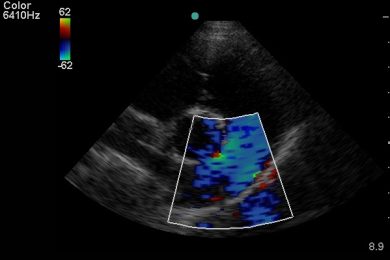

Cardiac ultrasound requires both technical image acquisition and specialist interpretation.

– High-quality echocardiography performed on-site by a trained Veterinary Sonographer

– Formal interpretation by a Board-Certified Veterinary Cardiologist within 48 hours

All studies are performed on site by a Veterinary Sonographer with over 20 years of ultrasound experience and are reviewed within 48 hours by a Board-Certified Veterinary Cardiologist. We offer: